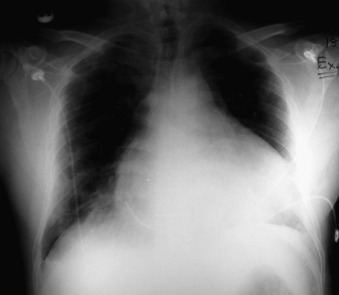

A pericardial effusion ( Figs. 16-1 to 16-15 ) is often suggested on the frontal chest radiograph by a smoothly distended, “flasklike” CPS. More than 500 mL of fluid must be present before the change in the CPS is fairly obvious. A flasklike appearance may be caused by myocardial disease as well; scrutiny of the hilar vessels may distinguish the two. In the presence of pericardial effusion, the hilar vessels are covered (the pericardium runs up onto them and obscures them). In the presence of myocardial disease, the hilar vessels are unusually prominent as they are distended under higher than usual pressure.

In a minority of patients with pericardial effusion, on the lateral radiograph, a stripe of radiolucent epicardial fat, a “fat line,” may be visible anteriorly, suggesting fluid in the pericardial space. A stripe greater than 2 mm is abnormal. This “pericardial stripe sign” is more easily seen in adults than children (more fat!).

A prominent azygous vein, superior vena cava, or inferior vena cava suggests cardiac tamponade.

Echocardiography is the diagnostic test of choice for the evaluation of pericardial effusions. Pericardial tamponade remains a clinical diagnosis, strengthened by supportive echocardiographic findings.